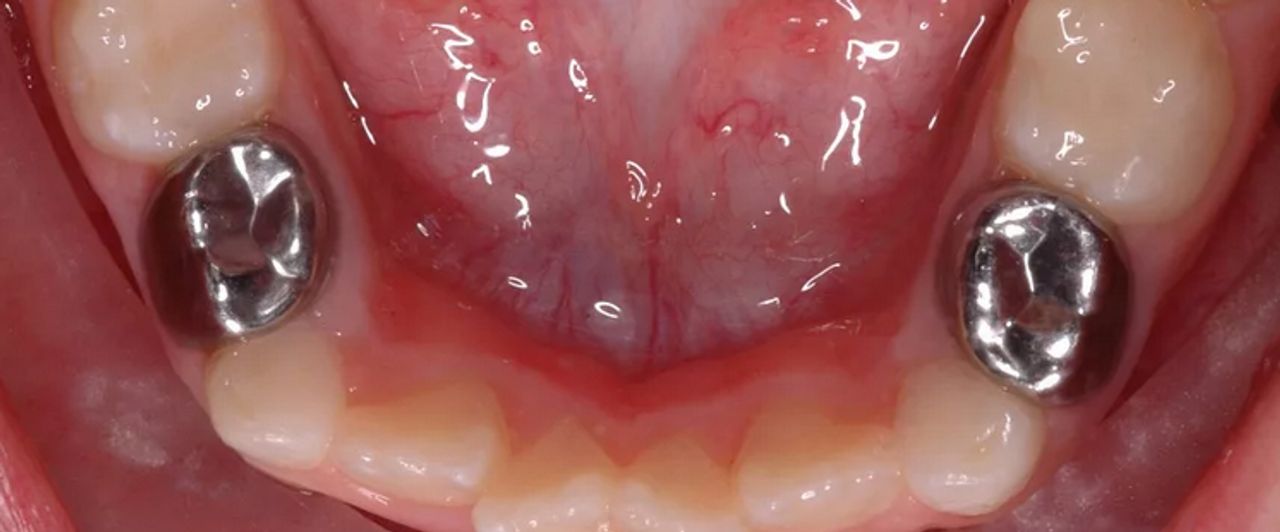

Эстетические реставрации в стоматологии детского возраста. Принимаем правильные клинические решения.

- Задачи терапевтической реставрации временных зубов.

- Параметры принятия клинических решений при реставрации зубов у детей.

- Предварительно подготовленные коронки (стальные vs циркониевые коронки).

- Предварительно подготовленные коронки (стальные и циркониевые коронки).